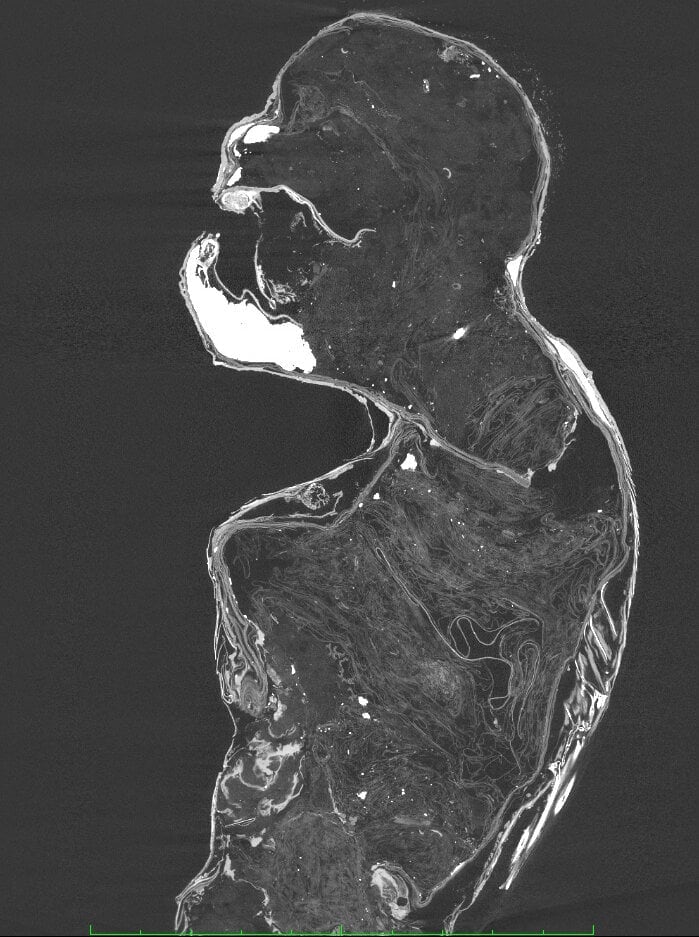

こちらが圓珠院に保管されている”人魚のミイラ”で、上半身に人かサルのような形が、下半身に魚のヒレやウロコの特徴が見られます。

全長は約30センチで、フィクション作品に登場するような人魚ほど大きくはありません。

頭部・眉・口の周辺に体毛があり、眼窩はまっすぐ正面を向いています。

耳があり、外耳道(耳の穴)も開口して、鼻および鼻孔も確認されています。

歯はすべて円錐形の尖った牙で、先端が後方(口の内側)に向けてややカーブしていました。

この口は明らかにサルのものと異なっていますが、調査ではその形状から肉食性の魚類のものと判明しましたが、種類までは明らかにできませんでした。

また目を引くのが、恐怖に怯えるかのように顔を覆う両腕です。

ここにはそれぞれ指が5本あり、平らな爪も付いています。しかしこの手もどうみてもサルのものとはことなります。

さらにこの上半身の肌には鱗が生えているのも確認できます。これもかなり異様な点と言えるでしょう。

下半身は背ビレや腹ビレ、尾ビレを持ち、全体がウロコに覆われています。

そして体表には砂や炭の粉を糊(のり)状のもので溶いた塗料が塗られていたようです。

そしてX線撮影の結果、非常に気になる事実が示されました。

上半身は下顎を除いて、骨格構造がまったく存在しておらず、これがサルの死体ですらないことが明らかになったのです。

この上半身は木や金属の心材も使わずに、内部は布や紙、綿で作られていたのです。

また首から頬、肩、腕にかけて見られた鱗の皮膚は、フグ科魚類の皮を貼ったものだとわかりました。

下半身の魚体部はスズキ目ニベ科の魚類の皮で覆われており、魚類の尾部骨格や、それぞれのヒレにおける担鰭骨(たんきこつ:魚類のヒレの基部にあって、それを支えている骨)が確認されています。

また、首の奥と下半身に金属製の針が見つかりました。